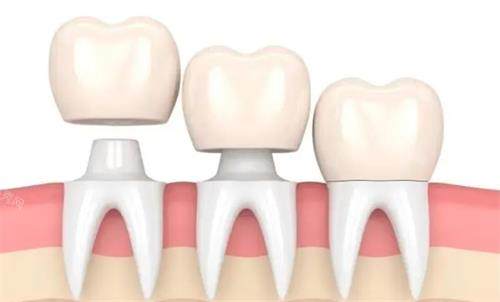

3. 戴冠的费用与类型:如何选择性价比?

金属烤瓷冠:800-1500元(美观性差,可能牙龈染色)

全瓷冠:2000-5000元(美观性好,生物相容性高)

嵌体:1500-3000元(适合牙体缺损较小者)

小编建议:后牙优先选全瓷冠(抗折性强),前牙可选氧化锆全瓷冠(透光性好)。